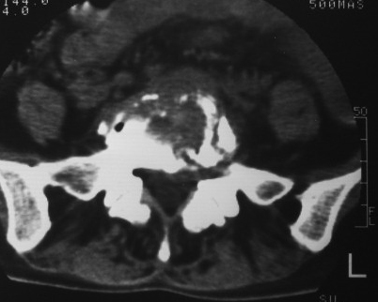

以下是引用dyqct在2007-3-1 18:04:00的发言:[br]腰5、骶1呈溶冰状骨质破坏,边界清楚,无明显硬化,内见多数沙粒状死骨,周围软组织肿胀。[br]考虑:腰5、骶1结核,建议严格抗结核治疗后复查。

以下是引用gaoxiao在2007-3-1 18:02:00的发言:[br]腰5骶1椎体见骨质破坏,其内见死骨形成,椎前软组织肿胀,感染性病变,腰骶椎tb。

以下是引用gaozhengyi在2007-3-1 19:39:00的发言:[br]骨质破坏并砂砾样死骨为椎体结核的表现。椎体结核骨质破坏区的特点是呈虫蚀状,常可见硬化缘。死骨表现为片状高密度影,正如本例。